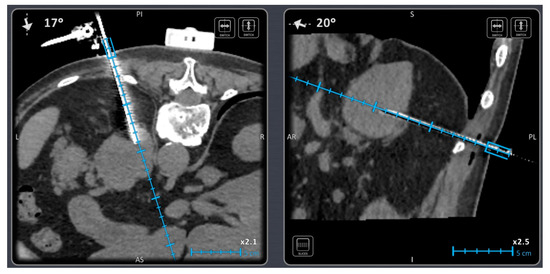

- Bale, R.; Widmann, G. Navigated CT-guided interventions. Minim. Invasive Ther. Allied Technol. 2007, 16, 196–204. [Google Scholar] [CrossRef] [PubMed]

- Bale, R.; Widmann, G.; Stoffner, D.R. Stereotaxy: Breaking the limits of current radiofrequency ablation techniques. Eur. J. Radiol. 2010, 75, 32–36. [Google Scholar] [CrossRef] [PubMed]

- Bale, R.; Laimer, G.; Schullian, P.; Alzaga, A. Stereotactic ablation: A game changer? J. Med. Imaging. Radiat. Oncol. 2023. [Google Scholar] [CrossRef] [PubMed]

- Fuhrmann, I.; Probst, U.; Wiggermann, P.; Beyer, L. Navigation Systems for Treatment Planning and Execution of Percutaneous Irreversible Electroporation. Technol. Cancer Res. Treat. 2018, 17, 1533033818791792. [Google Scholar] [CrossRef] [PubMed]